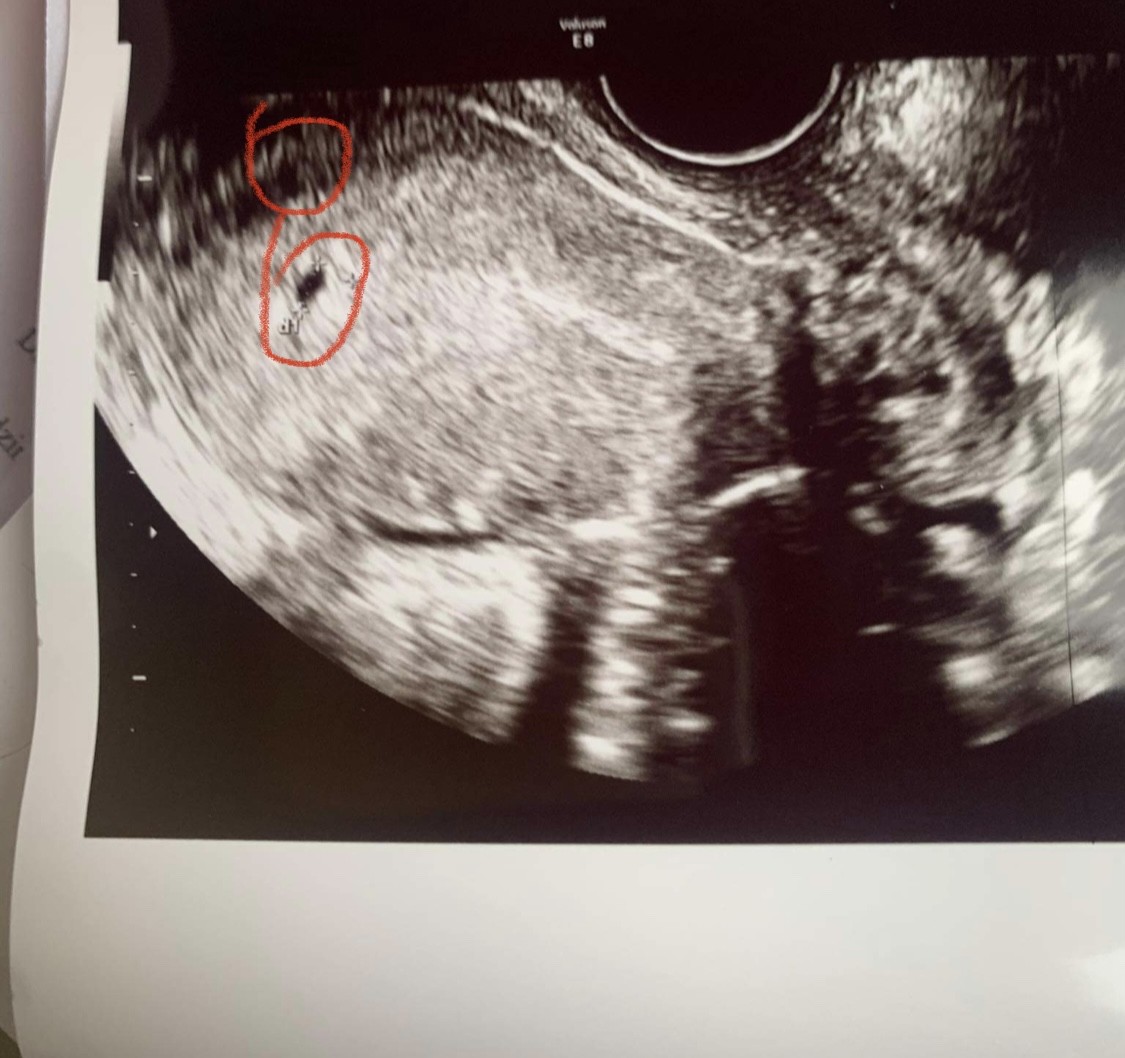

2 pecherzyki

Dzień dobry, czy tu są widoczne 2 pecherzyki?